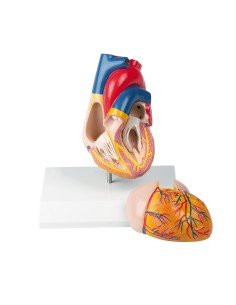

Du crâne en 22 parties à verrouillage magnétique aux modèles de colonne vertébrale, des modèles d'articulation aux modèles de cœur, chaque pièce de notre collection est conçue pour une immersion totale dans l'étude de l'anatomie humaine. Nos modèles, réalisés à partir de scans d'os réels, garantissent une expérience tactile authentique et une fidélité de poids presque identique aux originaux.

Indispensables aux étudiants comme aux professionnels, nos modèles anatomiques sont des outils pédagogiques qui permettent d'observer les structures anatomiques avec précision, en évitant les dissections ou les études invasives. Ils sont également utiles pour expliquer les pathologies aux patients, ce qui rend la communication plus efficace et permet de gagner un temps précieux.